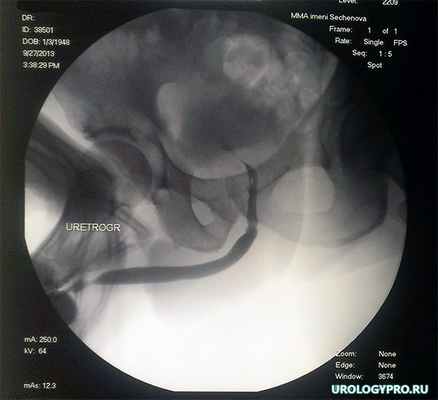

На рис. 5 представлены результаты ретроградной уретрографии через 2 недели после операции и удаления уретрального катетера.

Рис 5. Ретроградная уретрограмма. В зон анастомоза определяется незначительная неровность контуров уретры, сужения нет.

Цистостома удалена. При урофлоуметри максимальный поток мочи – 16 мл/с, средний – 9.2 мл/с при 180 мл мочи.

На повторной уретрограмме через три месяца значимых отличий не установлено (рис 6).

Рис 6. Уретрограмма через 3 месяца после операции